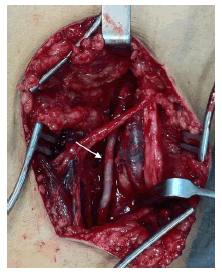

Con la confirmación diagnóstica de enfermedad quística de la adventicia, se decidió intervenirlo quirúrgicamente. Se utilizó un abordaje posterior de la fosa poplítea (figura 4) que expuso la lesión quística dependiente de la pared arterial. Se resecó el segmento afectado (figura 5) y se reparó el defecto con intercalación de injerto autólogo de vena safena (Figura 6). El paciente evolucionó favorablemente, sin complicaciones inmediatas. Acudió a control meses después de la cirugía, sin síntomas. Se practicó una angiografía por tomografía computadorizada (TC) de control, que demostró un adecuado flujo sanguíneo en el injerto (figura 7).

Se han descrito múltiples opciones terapéuticas, incluyendo la cirugía abierta o percutánea 12. El drenaje del quiste permite la reexpansión de la arteria; sin embargo, este abordaje suele fracasar por la viscosidad del contenido y las altas tasas de recurrencia 8,12. La angioplastia con balón no ha demostrado efectividad 8,10. La escisión del quiste con preservación de la arteria suele ser el tratamiento preferido. No obstante, para muchos cirujanos vasculares el tratamiento de elección es la resección del quiste y del segmento arterial afectado, con interposición de un injerto autólogo de vena 10. Esta aproximación, combinada con la ligadura de cualquier comunicación con la cavidad articular adyacente, reduce el riesgo de recurrencia 8,10.